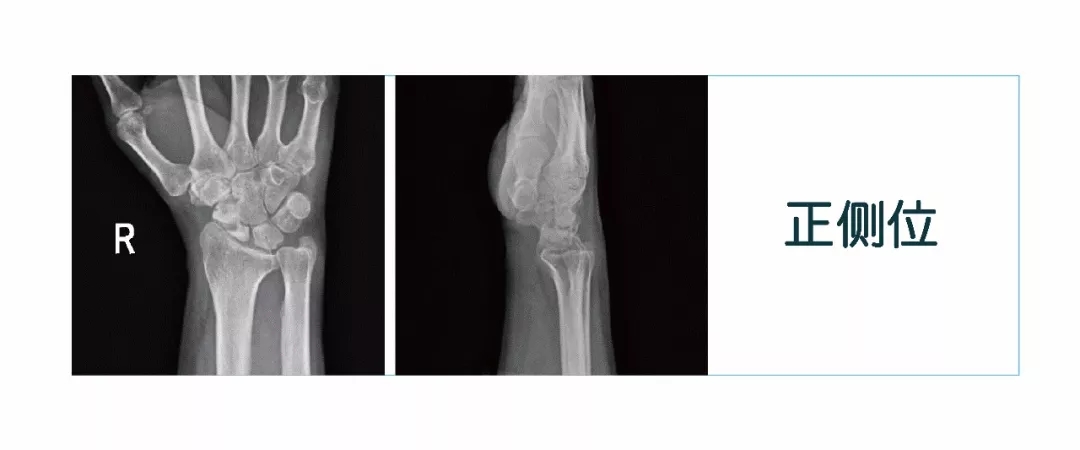

【朗润影像档案】20180126磁共振影像病例结果讨论